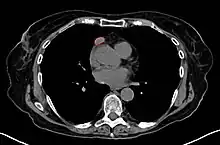

Another axial slice of a CT scan of the chest showing a small thymoma anterior to the heart (marked with the red line).

When a thymoma is suspected, a CT/CAT scan is generally performed to estimate the size and extent of the tumor, and the lesion is sampled with a CT-guided needle biopsy. Increased vascular enhancement on CT scans can be indicative of malignancy, as can be pleural deposits.[1] Limited biopsies are associated with a very small risk of pneumomediastinum or mediastinitis and an even-lower risk of damaging the heart or large blood vessels. Sometimes thymoma metastasize for instance to the abdomen.[5]